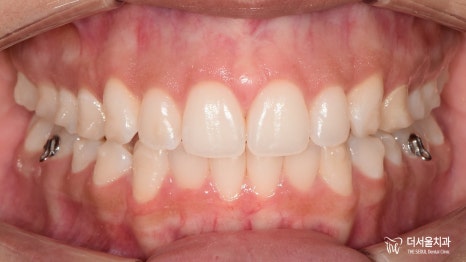

【 마무리 】

모든 치료가 마무리된 모습을 살펴볼까요?

이전과는 달리 훨씬 안정적인 모습의

맞물림이 관찰되고 있습니다.

교합은 물론이며 더욱 긴밀한 배열을

갖게 된 것을 볼 수 있는데요.

심미적으로나 기능적으로나

환자께서 좋아하실 수 있는 결과를 안겨드리게 되어

성남양심치과 도 정말 뿌듯했답니다^^